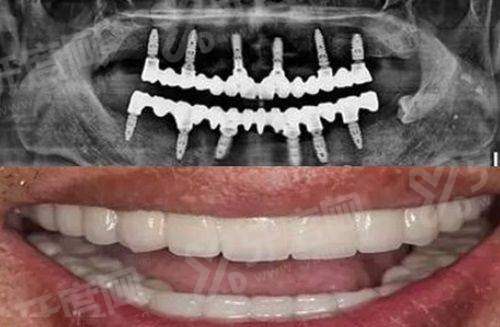

8. 半口种植牙价格:30000元起

9. 全口种植牙价格:60000元起